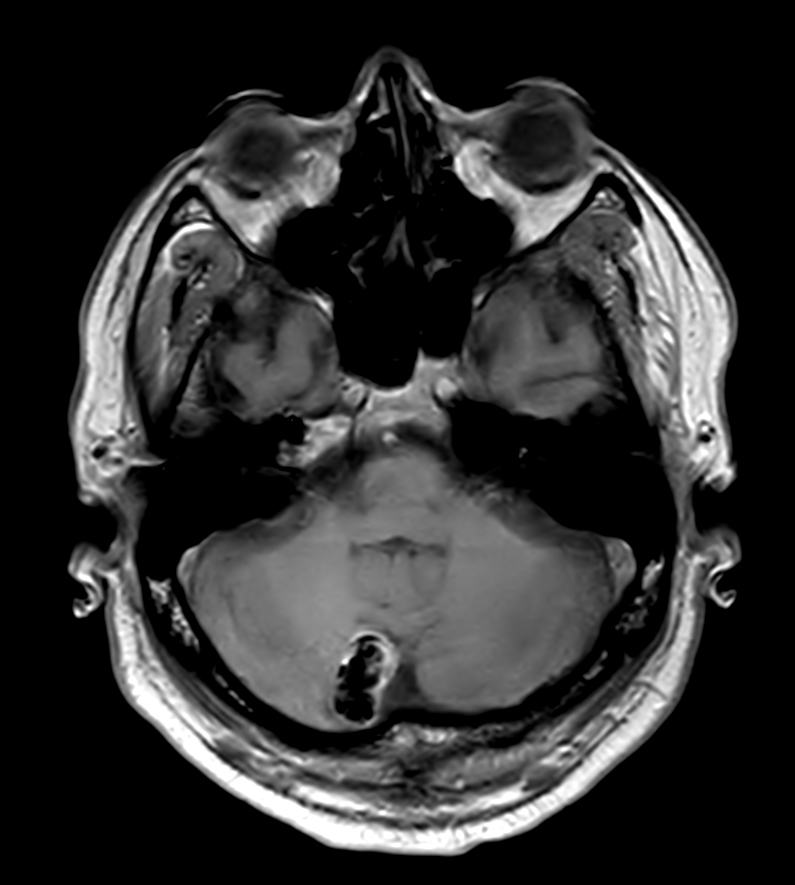

Patient with a lesion in the cerebellum. The ExamCard includes Compressed SENSE to accelerate the entire exam and techniques for motion reduced imaging (MultiVane XD), 3D imaging to acquire high resolution data in multiple directions, 3D susceptibility weighted imaging (SWIp), angiography sequences (Time-of-Flight and Contrast-Enhanced MRA with both arterial and venous phases), DTI with MultiBand SENSE to acquire a high number of diffusion directions in a short scan time and EPIC Brain to bring down any residual distortion.

T2w TSE MultiVane XD